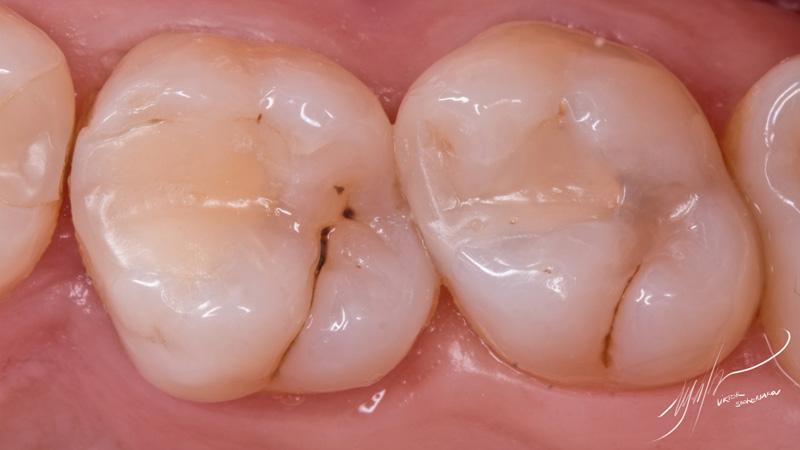

В данном клиническом случае проводилась реставрация зубов 1.6 и 1.7. Часть полостей была заполнена материалом SDR для смягчения воздействия полимеризационного стресса на композит, а также для более быстрого заполнения части внутреннего объема.